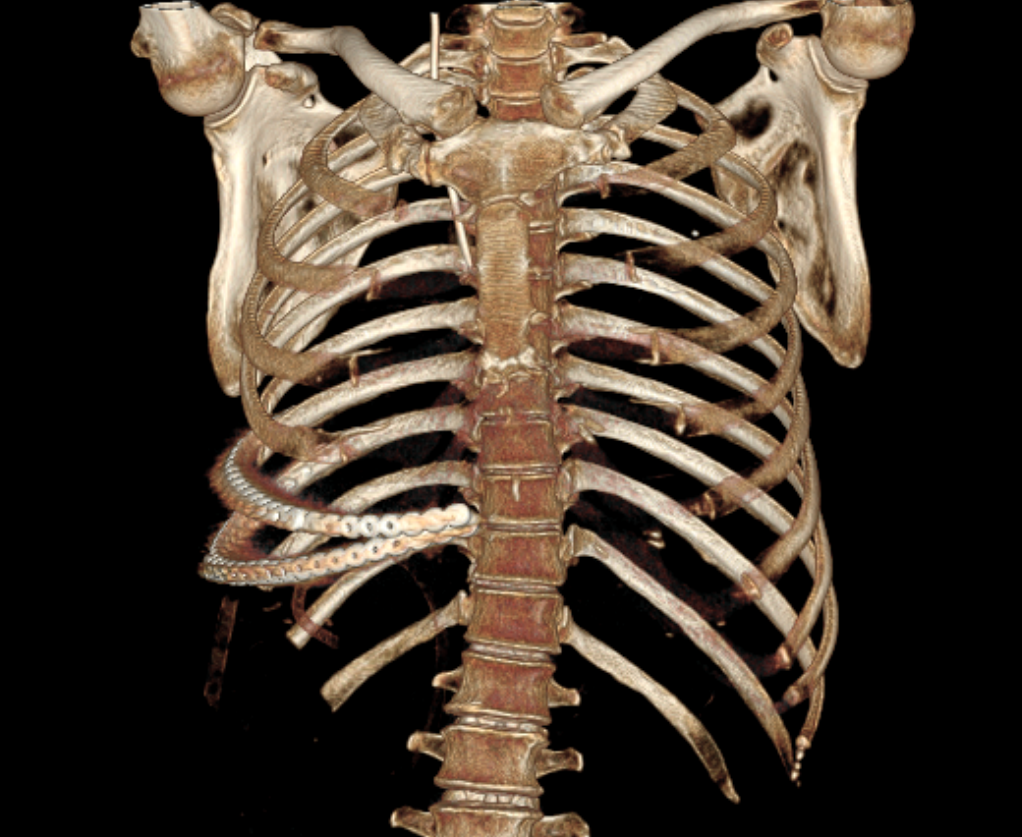

3D模拟肿物与周围脏器关系,正视图与侧视图(黄色为肿物)

通过360度旋转、分层透视,肿瘤与肋骨、肝脏、结肠、右肾以及临近大血管的解剖关系一目了然:肿瘤起源于第7,8肋骨,向胸腹腔内膨胀性生长;肿瘤上界与肝脏S5、S6段分界不清,需要术中探查明确情况,必要时需要切除部分肝脏;结肠及右肾虽毗邻肿瘤边界,但尚未被肿瘤浸润,为功能保留提供可能。

“3D数字医学重建技术不仅可以帮助我们评估手术边界,还提前模拟了术中可能遇到的血管变异和脏器保护难点,让我们能够在完整切肿瘤的同时,尽最大努力保留患者的正常器官组织。”到会的肝胆胰外科古松钢副主任、泌尿外科许哲主任 、胸外科陈少斌副主任、胃肠外科林桂兴主治医师等专家均对3D数字医学重建技术表示认可并讨论制定专科手术协助方案。在充分的讨论后,基于这一“导航图”,MDT团队最终确定了“整块切除受累肋骨及部分肝脏,分离保护结肠及右肾”的手术方案。